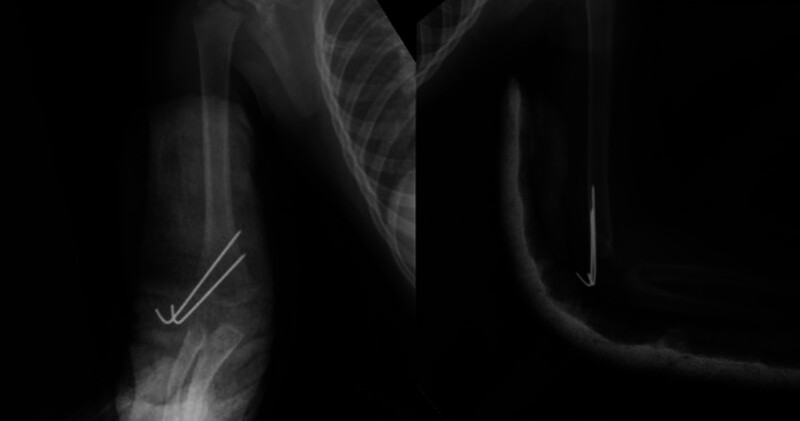

小儿肱骨外侧髁骨折(PHLCF)是儿童中最常见的骨折之一。PHLCF约占所有小儿肘部骨折的20%。治疗方法包括:夹板固定的非手术治疗、经皮K线固定闭合复位术(CRPP)和K线固定开放复位术(ORIF)。我们的目的是评估采用 CRPP 或 ORIF 治疗 Jakob 2 型 PHLCF 的放射学、功能和临床疗效。我们假设 CRPP 与 ORIF 对 Jakob 2 型 PHLCF 的治疗同样安全有效。在这项回顾性研究中,我们纳入了在一个中心接受手术治疗的 Jakob 2 型 PHLCF 患者。研究排除了多发性骨折或开放性骨折患者。研究共纳入 69 名 2 至 12 岁的患者,并将他们分为两组。第一组包括接受 CRPP 治疗的患者,第二组包括接受 ORIF 治疗的患者。研究人员对患者的人口统计学、放射学、临床和功能参数进行了评估。平均手术时间(P

Pediatric humerus lateral condyle fractures (PHLCF) are one of the most common fractures among children. PHLCF is approximately 20% of all pediatric elbow fractures. Among the treatment modalities are: nonoperative treatment with splinting, closed reduction with percutaneous K-wire fixation (CRPP), and open reduction with K-wire fixation (ORIF). We aimed to evaluate radiological, functional, and clinical outcomes of Jakob type 2 PHLCF treated either with CRPP or ORIF. We hypothesized that CRPP may be as safe and effective as ORIF for Jakob type 2 PHLCF. In this retrospective study, we included patients with Jakob type 2 PHLCF operatively treated in a single center. Patients with multiple fractures or open fractures were excluded from the study. 69 patients between ages 2 and 12 were included and they were divided into two groups. Group 1 included the patients treated with CRPP, whereas Group 2 included the patients treated with ORIF. Demographical, radiological, clinical, and functional parameters were evaluated. Average duration of surgery ( P  < 0.001), initial displacement ( P  = 0.014), and duration of admission ( P  < 0.001) were significantly less in group 1. Group 2 had significantly higher percentage of left-sided injury than group 1 ( P  = 0.038). Average varus deformity score was significantly higher in group 1 ( P  = 0.014). CRPP was associated with shorter duration of surgery and hospital stay. Functional, clinical, and radiological outcomes were identified similar between CRPP and ORIF for Jakob type 2 PHLCF. CRPP may be as safe and effective as ORIF for Jakob type 2 PHLCF.